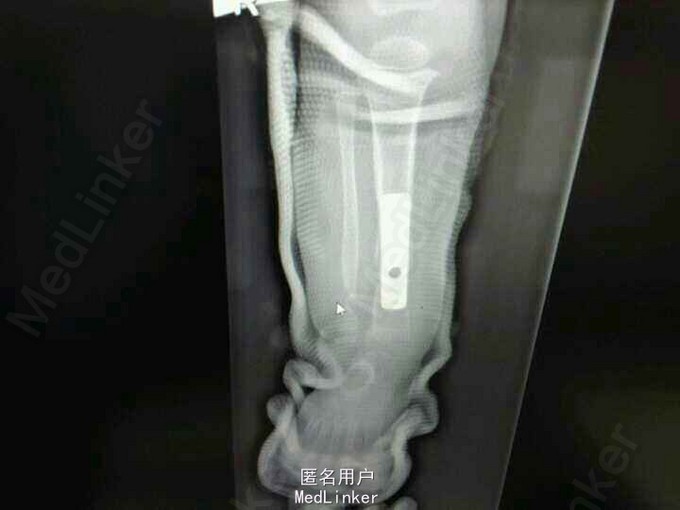

患女1岁8个月,患者母亲诉小孩出生时右小腿畸形,1岁时学走路跌倒后哭闹数天,小腿肿胀去医院检查示右胫腓骨折,稍做固定,1岁3个月时复查骨折未愈合,考虑先天性胫骨假关节,行手术治疗,现术后5个月复查未愈。目前小儿不能行走。

神经纤维瘤病,先天性胫骨假关节。该患者经过讨论及与家属多次沟通愈后情况,行病灶切除,取母体骨移植,AO锁定钢板内固定,暂时管型石膏外固定,并订制支具